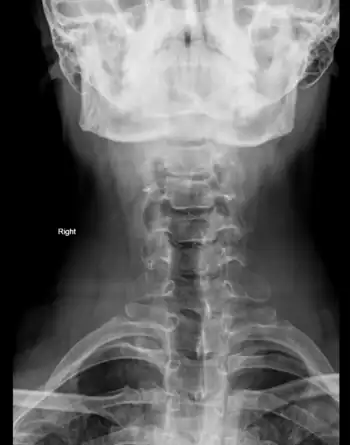

| C7 spinous process. | |

Clay-shoveler's fracture is a stable fracture through the spinous process of a vertebra occurring at any of the lower cervical or upper thoracic vertebrae, classically at C6 or C7.[1] In Australia in the 1930s, men digging deep ditches tossed clay 10 to 15 feet above their heads using long handled shovels.[2] Instead of separating, the sticky clay would sometimes stick to the shovel. At the top of the arc of motion, with the arms extended, the worker may hear a pop and feel a sudden pain between the shoulder blades, unable to continue working.[3][4] The mechanism of injury is believed to be secondary to muscle pull and reflex with force transmission through the supraspinous ligaments. The tremendous force pulls on the spinous process producing an avulsion fracture. The fracture is diagnosed by plain film examination.